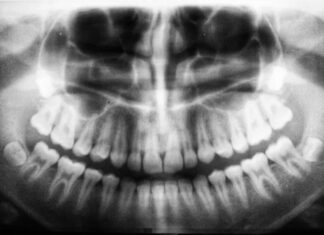

Osteoporosis and jaw

Osteoporosis is often described as a "silent" disease in the sense that it is rarely accompanied by clinical manifestations in its early stages.

Grinding teeth: What is it and how is it treated?

Bruxism is the scientific term used to describe a morbid condition characterized by unconscious grinding...